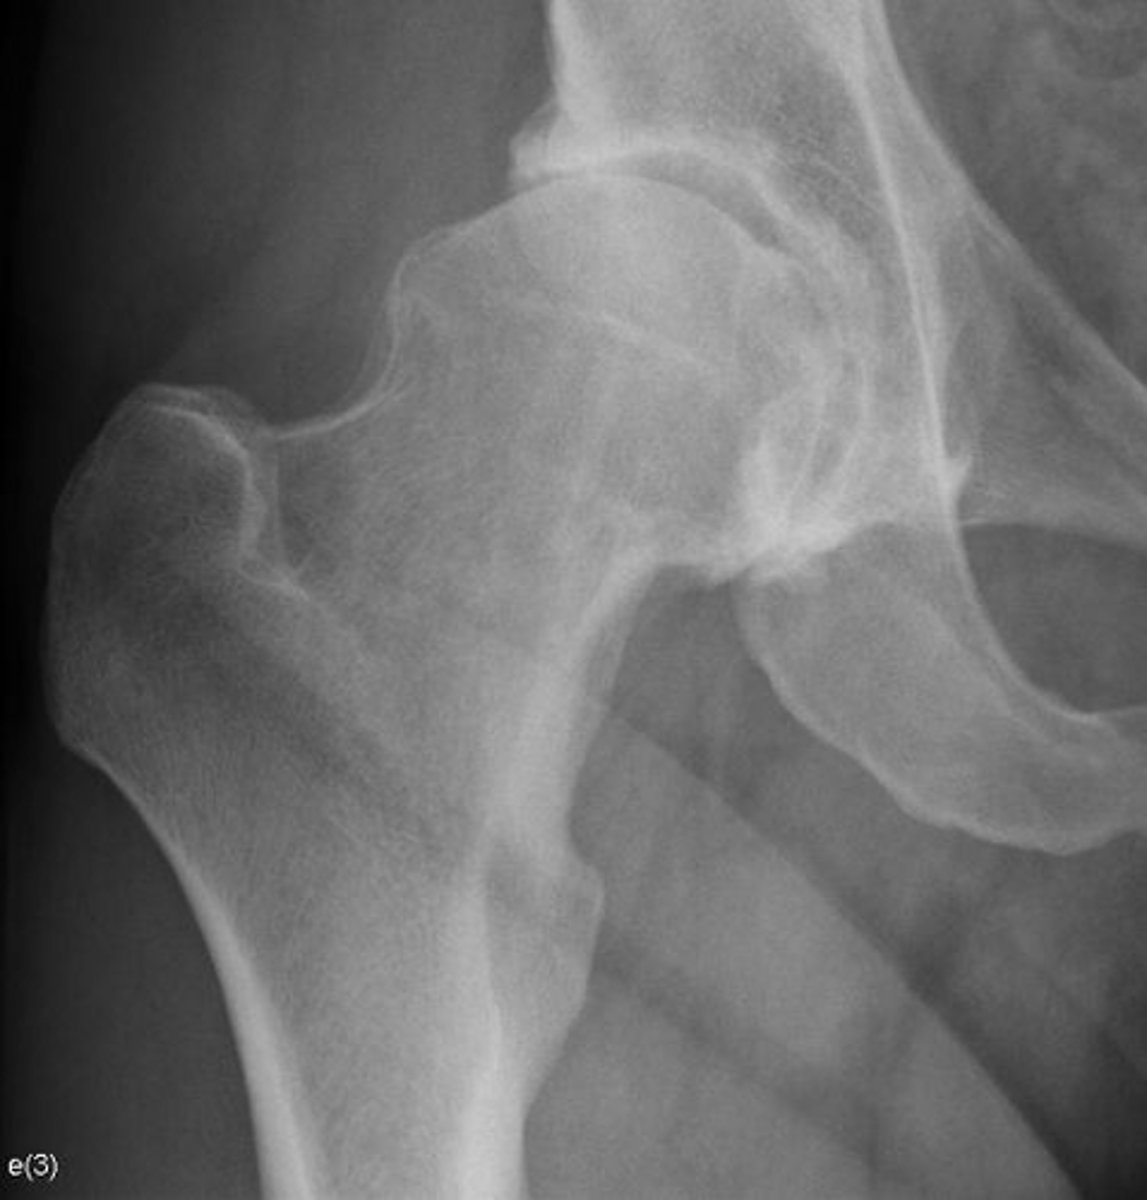

Right hip

Bone

Right femoroacetabular joint

Joint

Yes

Joint space narrowed?

Non-uniform

Uniform/non-uniform narrowing

No

Periarticular erosions

Osteophytes

Subchondral cysts

Subchondral sclerosis

Periarticular osteopenia

Soft tissue swelling

Intra-articular calcification

Joint ankylosis

Extra-articular calcification/osseous bodies

Subluxation

Dislocation/diastasis

Bilateral

Bilateral/unilateral

Degenerative

Category of joint disease

Osteoarthrosis

Most likely diagnosis?

Orthopedic referral

Next step?

- Collapse

- Step-off deformity

- More fragmentation

How can you differentiate this from avascular necrosis?

- CAM deformity

- Yes

- What "deformity" of the femoroacetabular joint is present?

- Do you think it relates to the diagnosis?

Would you adjust this patient?